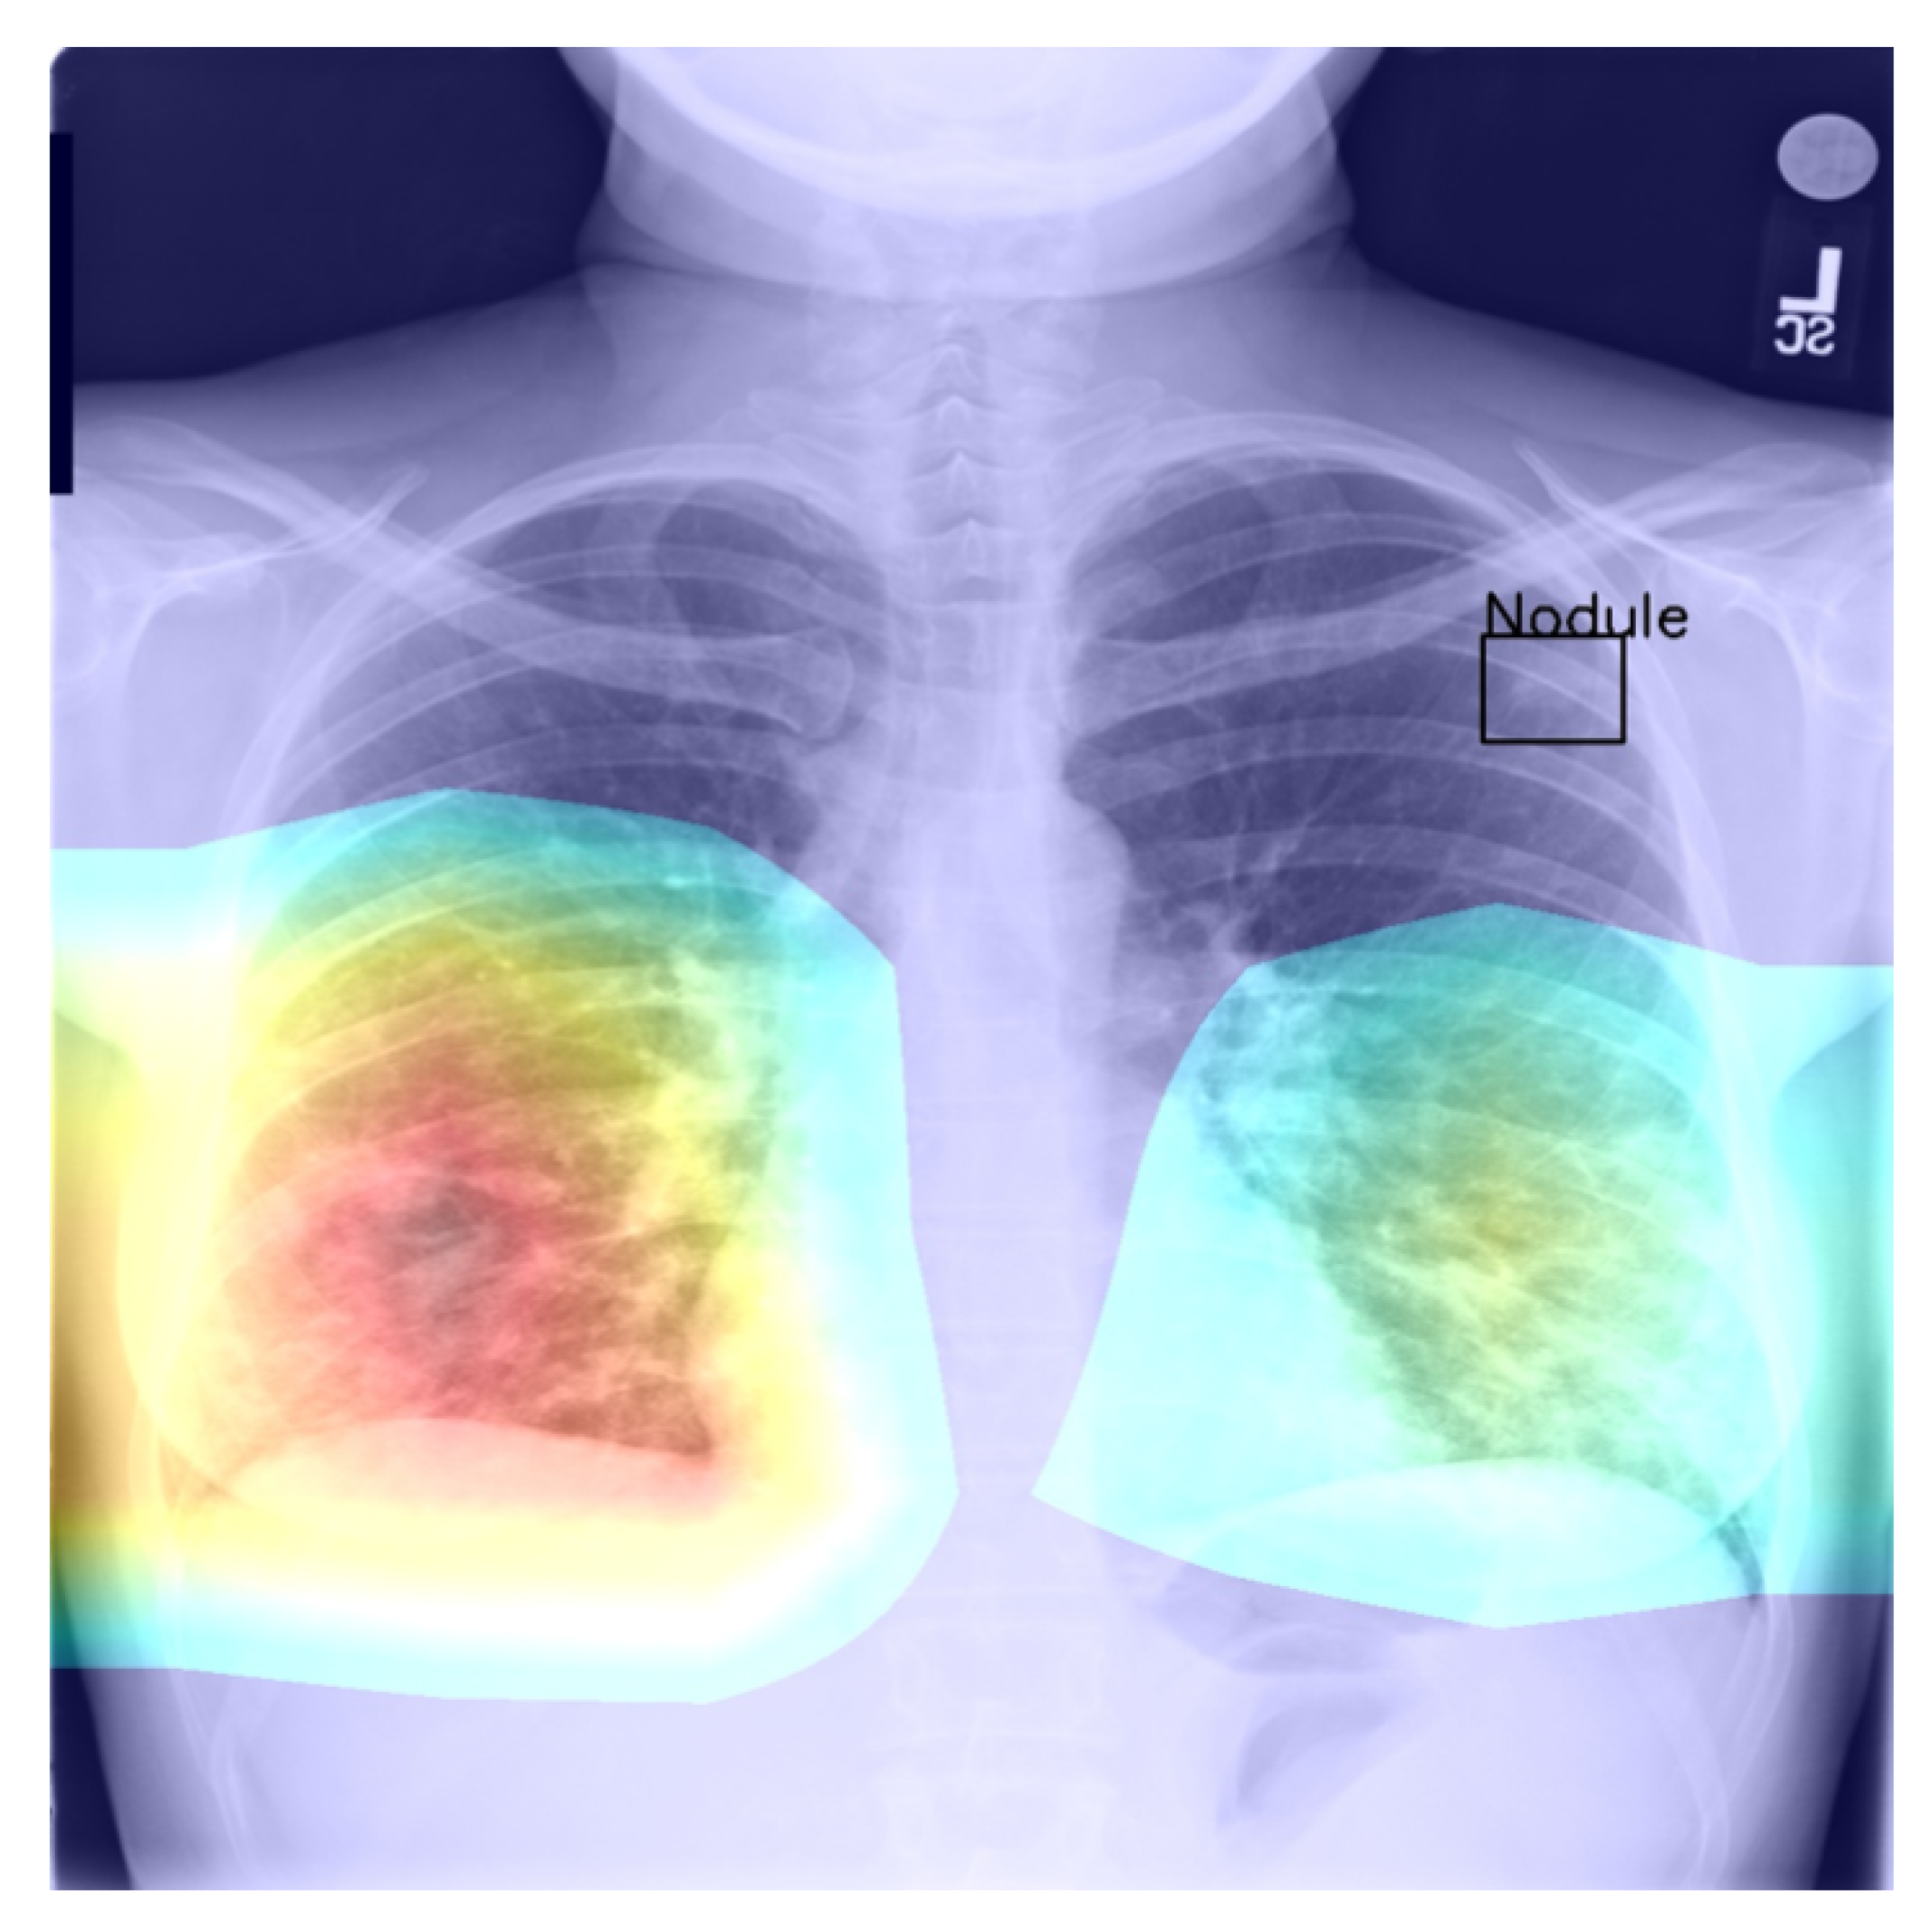

4.4. Saliency and Explainability

As we noted previously, using Grad-CAM, or indeed similar methods [27], it is possible to quantify and thus visualise the importance of different parts of an analysed image a network uses as the basis for its prediction. This can be helpful both in understanding why the model fails when it does as well in focusing an expert’s attention for further analysis and interpretation.

Using the bounding boxes information provided, we further examined how well the models performed in localizing the visual presentation of different diseases. We quantified this using the intersection over union (IoU), a ratio of the intersection of the bounding box and heat map activation and the union of the area they both cover, which can be loosely related to the well-known Bhattacharyya coefficient, a measurement of the amount of overlap between two statistical samples [28,29]. The ratio was calculated using thresholded heat maps with the key findings summarised in Table 6 and Table 7.

These findings are interesting in the context of the previously discussed AUROC-based comparison. Although the modified model performed better in terms of the former performance measure, that is to say AUROC, here, we found that it is the standard that does a better job in localizing the diseases. The likely explanation for this apparent paradox can be found in the structure of the network that was introduced in Section 3 and shown in Figure 1 and the flow of the metadata information and the manner in which it is used in the backpropagation. In any event, the important lesson to draw here is the same one that pervades the present article: any model must be examined in a variety of different ways and its performance measured using a range of comprehensive metrics and with a keen eye on their clinical significance, and its failure modes must be identified and understood, before any application in the real world is even considered.

Returning to the findings in Table 6 and Table 7, it is a concerning fact that the minimum IoU for all classes was found to be zero (an interesting example is shown in Figure 4. In other words, in the case of every class, that is disease, there was at least one instance in which the ground truth bounding box had no intersection with the thresholded saliency heat map. The models did, however, perform rather well in many cases, as indicated by the average scores. To check for potential biases, we measured the Pearson’s correlation coefficient between the number of class instances and the corresponding mean IoU and found it to be −0.265. This is an interesting and perhaps somewhat surprising finding, which should be revisited in future work. On the present evidence, we hypothesise that the more numerous classes exhibited greater variability in appearance presentation, which affected the performance under the IoU measure.

Figure 4.

Example of a high-confidence correct label identification, despite the entirely incorrect disease localisation.